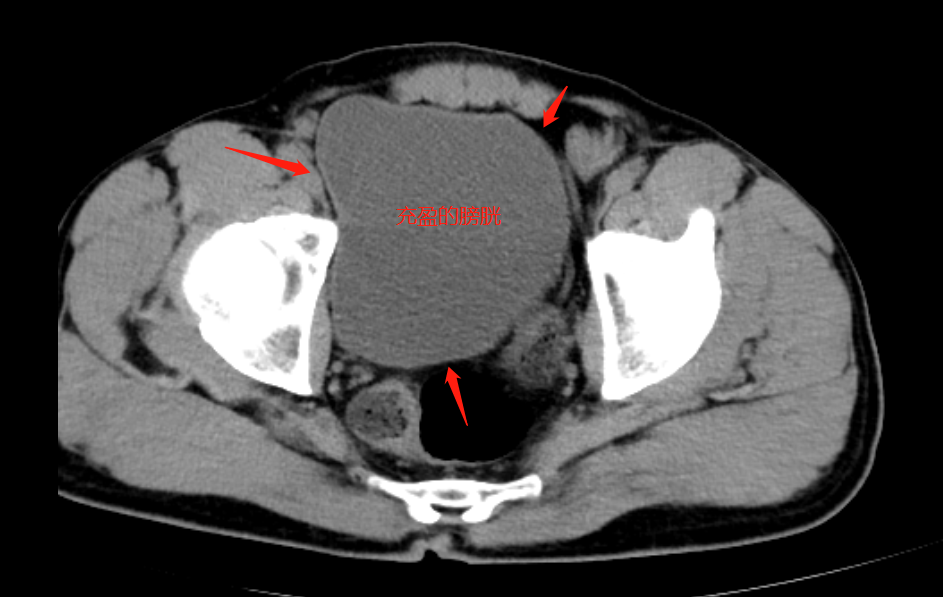

这是因为胃里的水进入血液循环,再通过肾脏形成的尿液,暂时持续储存在膀胱中,需要一定的时间,而膀胱作为盆腔的重要器官,是盆腔CT观察和描述的重点内容之一,所以需要在充盈状态下得出准确的判断。同时,充盈的低密度膀胱作为一个良好的背景,可以更好地显示前列腺或子宫情况。